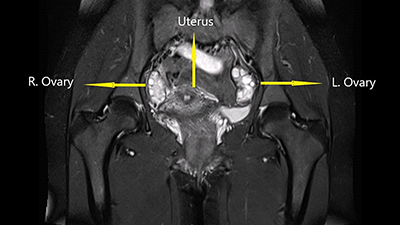

L'endometriosi è una condizione che si sviluppa quando porzioni della mucosa che riveste internamente l'utero, detta endometrio, si sviluppano al di fuori di questo (Fig. 1) e, pur non trovandosi nella loro sede fisiologica, svolgono le loro normali funzioni; ne consegue che ogni mese, sotto lo stimolo degli ormoni prodotti dalle ovaie, si ispessiscono e si sfaldano, provocando una "pseudo mestruazione" che causa dolore talvolta molto intenso, specialmente durante il flusso mestruale.

Figura 1. Presenza di tessuto endometriale al di fuori della cavità uterina.

Le sedi più frequenti di impianto anomalo di tessuto endometriale sono le ovaie, le tube di Falloppio o l'interno della pelvi (parte bassa dell'addome) che comprende organi quali vescica e intestino. La presenza di endometrio al di fuori degli organi pelvici è molto rara.